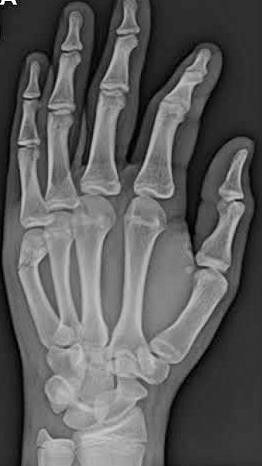

A detailed history taken before the patients were subjected for the surgery. The patients were also subjected for the detailed physical examination. X-ray with AP, oblique/lateral views were done, Routine investigations as per the institution protocol were sent. All the patients were subjected for Pre-anesthetic check-up and clearance. In case of open fractures, debridement of the wound and thorough irrigation was done with normal saline.

Closed/open reduction was achieved by traction and manipulation. To maintain reduction, percutaneous Kirschner-wire or Joshi’s external stabilization system were used. Image intensifier (C-arm) was used as a guide for the steps mentioned above. Post-operatively, x-rays were taken to evaluate the fixation. Patients were taught active mobilization of the unaffected fingers, elbow and shoulder from immediate post-op period. Pin tract dressings were done regularly. Patients were called for periodic evaluation at 2 weeks, 4 weeks, 6 weeks and 8 weeks on OPD basis to assess: